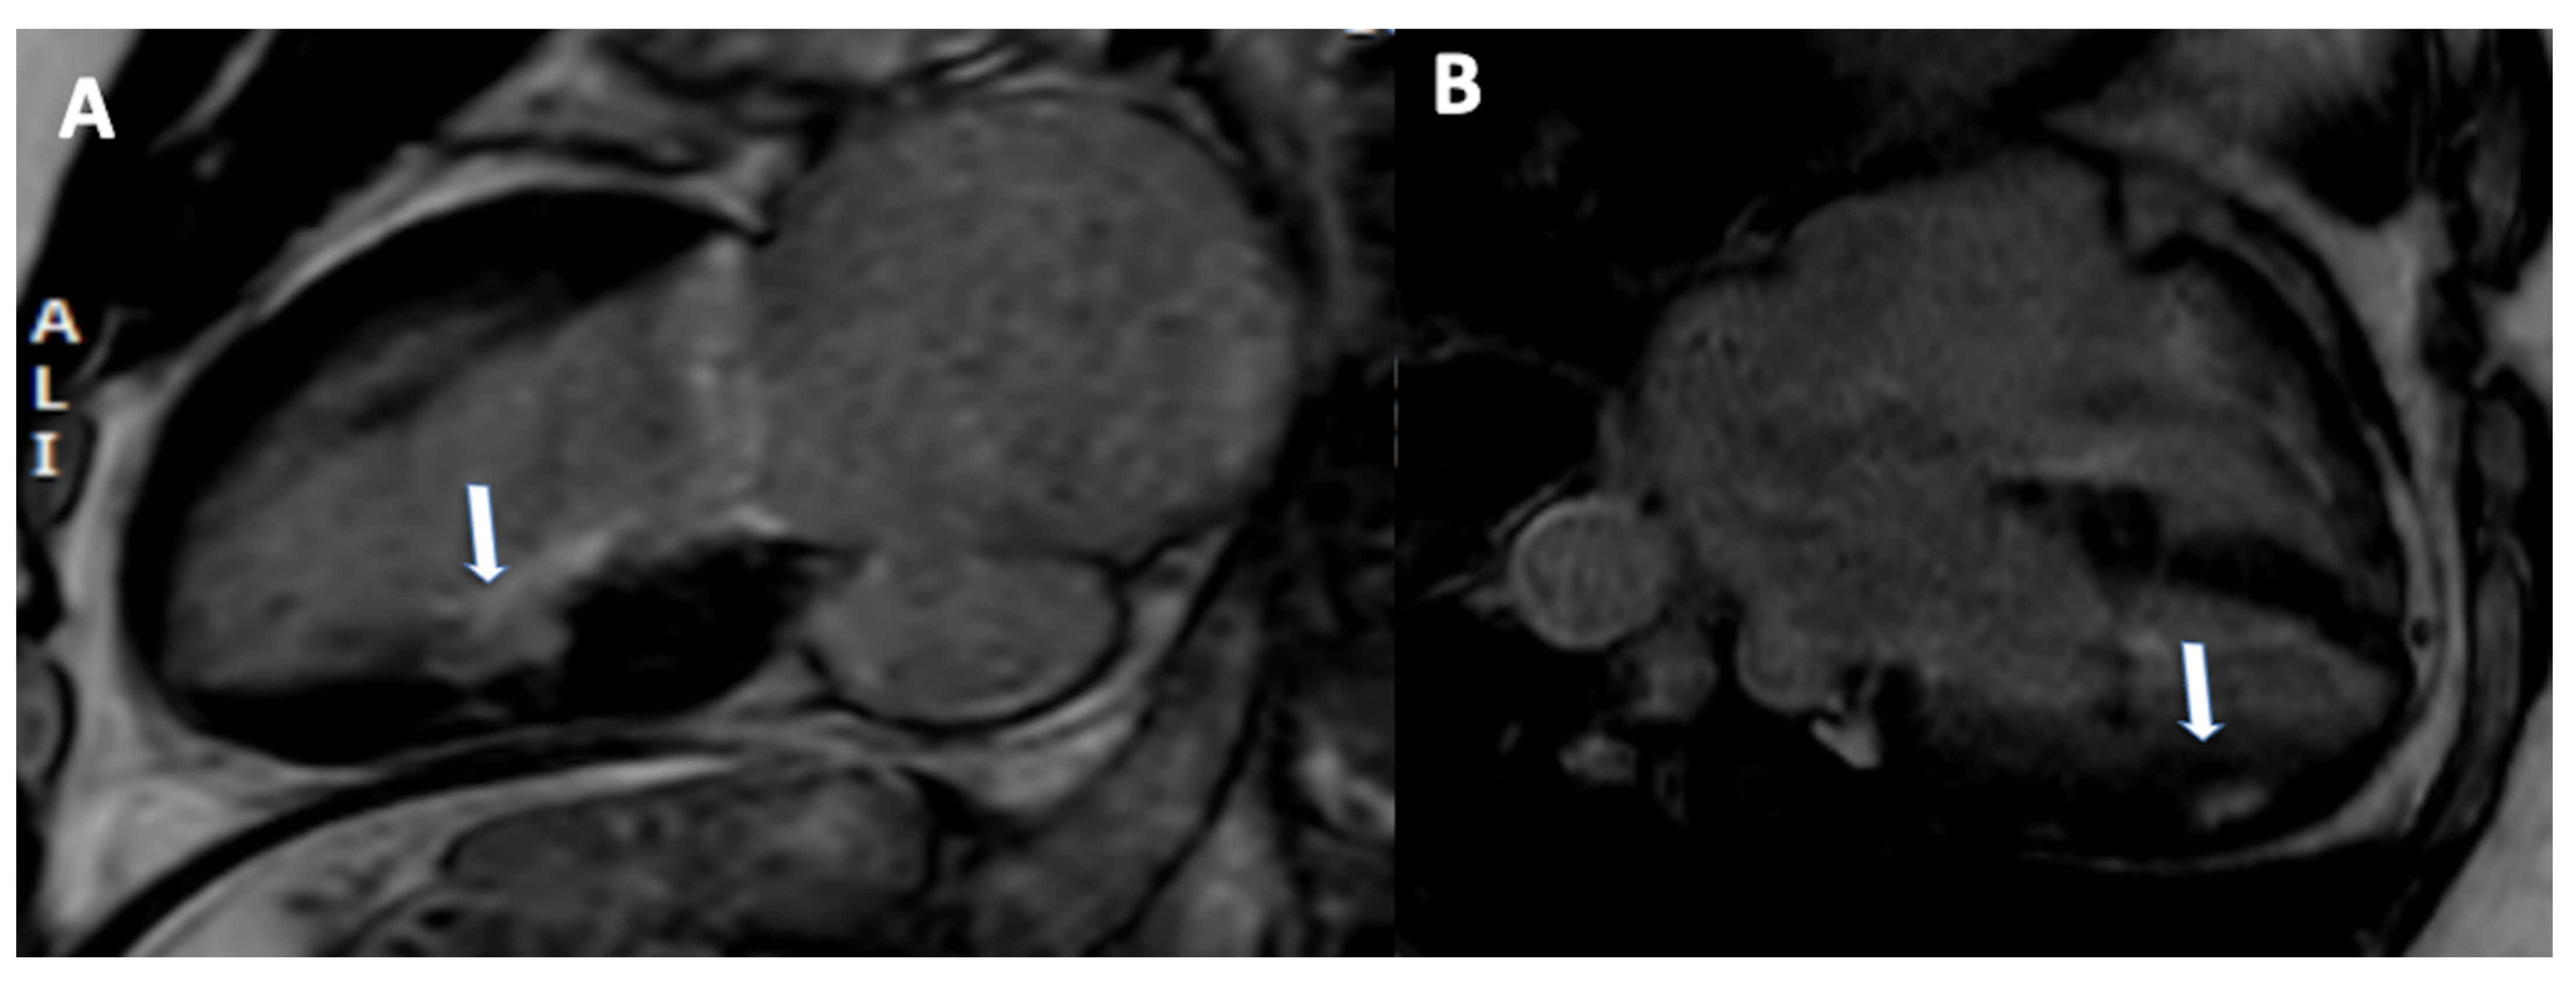

3.2. CMR Tissue Characterization